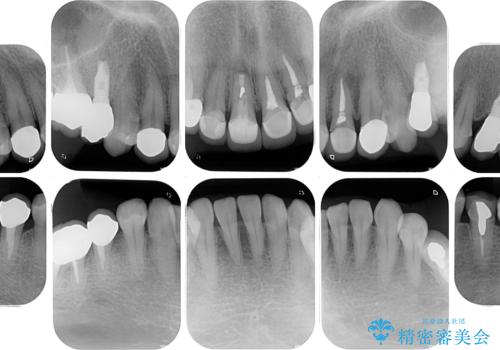

右下のむし歯が歯肉縁下に及んでおり、歯周外科処置(歯冠長延長術)を行った上で、根管治療を行い、状態を整えて補綴治療を行うこととしました。

上顎前歯の根尖病変に痛みがありましたが、既に前歯が補綴治療済みであっため、外科的歯内療法(歯根端切除術)を行うことで解決することとしました。

新幹線で通院をされていたため、極力診療回数を減らして、一度にまとめて多くの処置を行うことで負担を軽減しました。